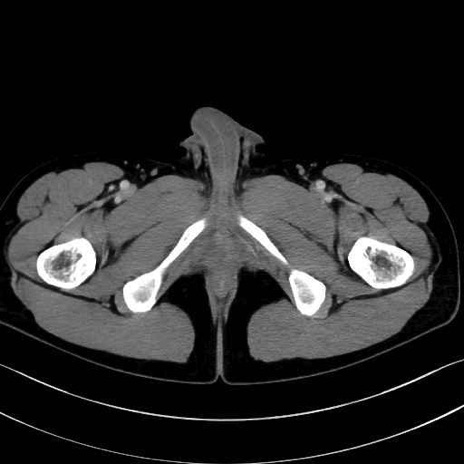

中殿筋(gluteus medius)のCT画像の解剖

症例